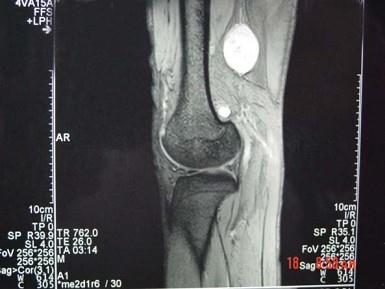

问题 男,48岁,腘窝上方疼痛2年余,呈持续性钝痛,且疼痛逐渐加重,曾以"结核”治疗无明显好转,体检腘窝上方肿胀,局部压痛,实验室检查均正常,请结合所提供的图像,选择最佳选项 ( )

选项 A、腘窝上方神经鞘瘤 B、腘窝上方脓肿 C、腘窝上方血管瘤 D、腘窝上方肌腱神经纤维瘤 E、腘窝上方囊肿

答案 D